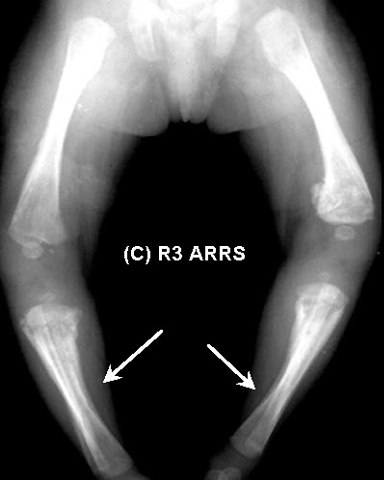

Infantile congenital Presenting With Bilateral

Radiology A skiagram of the child's skeletal system showed hyperostosis oftl* upper end ofeach humerus, moremarkedonleft analysis of 88 cases of congenital syphilis. An en-larged testis in an infant below the age of 4 to 5 months should arouse suspicion of congenital ... Read Content